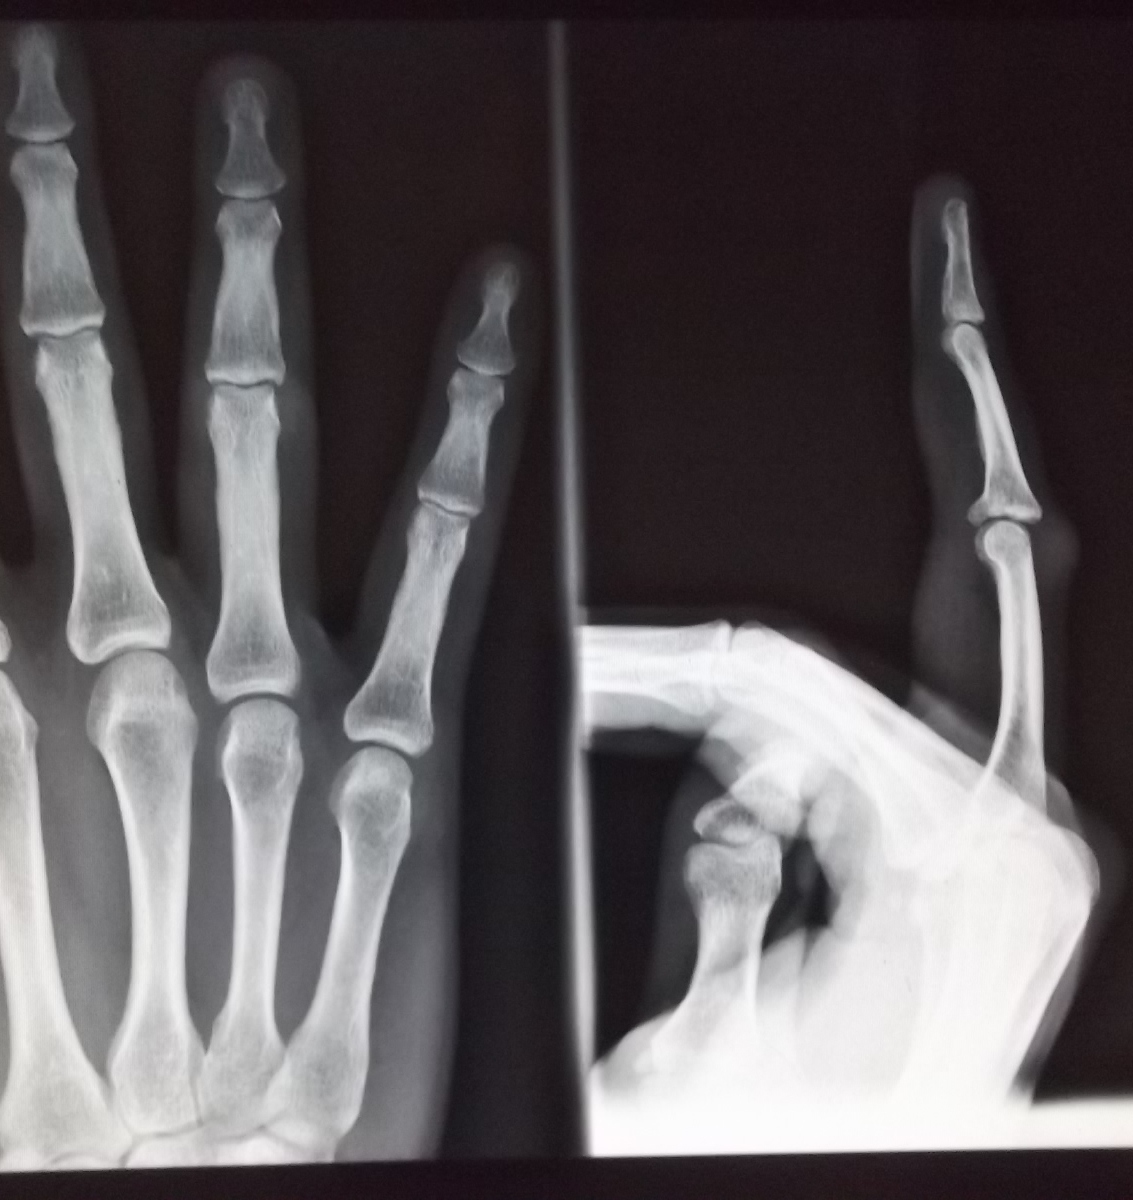

Buongiorno nel 2010 a seguito di compressione e stiramento di una fune attorno alla mia mano (tiravo una fune insieme ad altre persone in fila e l'ho avvolta intorno alla mano per fare maggiore presa ma purtroppo le persone dietro di me hanno bruscamente tirato la fune che mi ha stretto violentemente la mano) ho avuto una frattura alla base della falange intermedia del 4° dito della mano destra. Ho messo la stecca e dopo averla tolta ad oggi in corrispondenza della frattura ho un ispessimento del dito o gonfiore rigido. Convinta che l'osso non fosse stato riposizionato nella sua posizione corretta ho rieseguito una RX ed è tutto ok. Riesco a muovere interamente il dito. Di cosa di tratta questo ispessimento poco estetico non trattandosi di osso? Come posso risolverlo per ridurlo ed attenuarlo? Che accertamenti fare?

Commento file: Dopo la stecca ovvero adesso

DOPO.jpg

Commento file: Prima della stecca

PRIMA1.jpg

DITO2.jpg

Dal 2010 sono passati 6 anni !??!! Certo mi mandi foto del dito e della radiografia . A presto